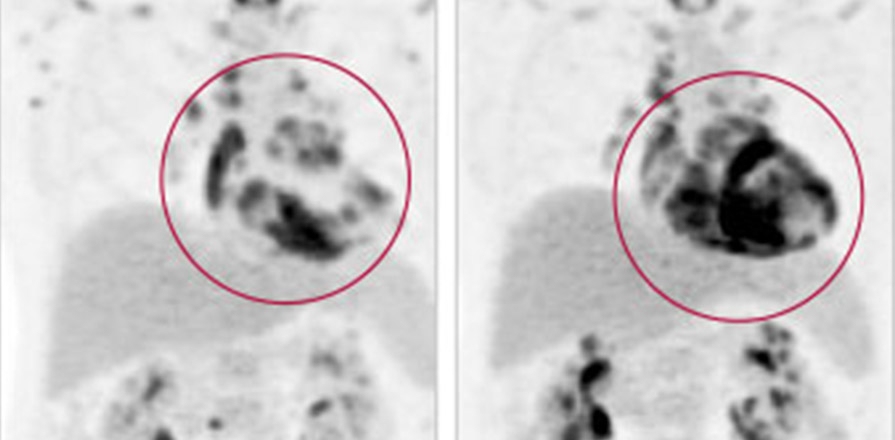

Image of cardiac sarcoidosis

Fellow Daniel Juneau, MD, and his colleagues in the Cardiac PET Research Team examined patterns of sarcoidosis outside of the heart in patients who underwent a type of imaging called positron emission tomography (PET)-CT after being diagnosed with acute cardiac sarcoidosis. In the 18 patients studied, almost 90% also had disease in their lymph nodes and about 60% had disease in organs other than the heart. The percentage that had sarcoidosis in the lungs (just under 40%) was much lower than in previous studies. Only one patient had disease confined to the heart, known as isolated cardiac sarcoidosis.